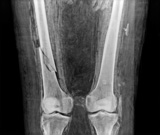

5.

ミイラ(脚) Mummy image (leg)

古代エジプトのミイラの右大腿骨骨折部位は,周辺に新しい骨の成長が見られないことから,死亡後,ミイラ化された後に折り曲げられたことを示している。

撮影および画像提供: フィールド博物館 |